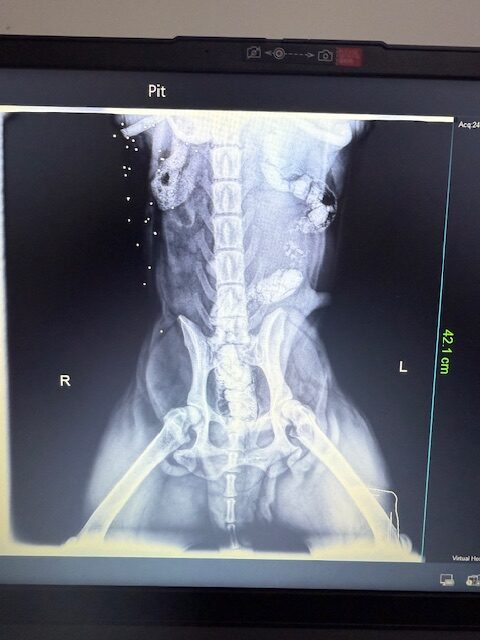

Peaches was rescued from Ramlet el Bayda. She was shot by an official from the municipality. Her leg was completely shattered. We had to amputate! She’s very mellow, sweet and is good with other dogs. DOB: 8/8/2017